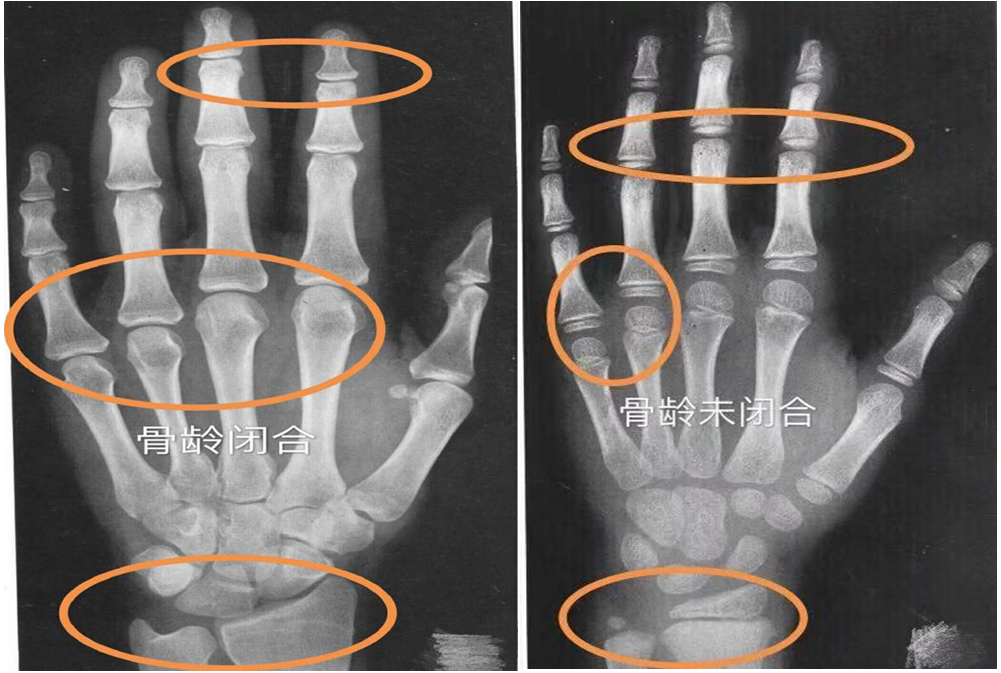

矮小、性早熟门诊主任刘静介绍,人的身高增长是有时限的,临床医学表明,一般情况下,人的骨骺在14-15岁就会闭合,一旦骨骺闭合,任何方法都不可能再长高。因此,家长需要尽早关注孩子身高,早发现身高落后或过早发育,尽早来就诊评估。说到评估身高,不得不提骨龄。人的生长发育可用两个“年龄”来表示,即生活年龄(日历年龄,CA)和生物年龄(骨龄,BA)。临床上通过拍摄左手腕部的X光片,观察指骨,腕骨及桡、尺骨下端的骨化中心出现的时间、大小、形态等,诊断骨骼实际发育程度,来确定骨龄。骨龄能较准确地反映生长发育水平和成熟程度,了解儿童的生长潜能以及性成熟的趋势,是预测儿童的成年身高的重要依据。